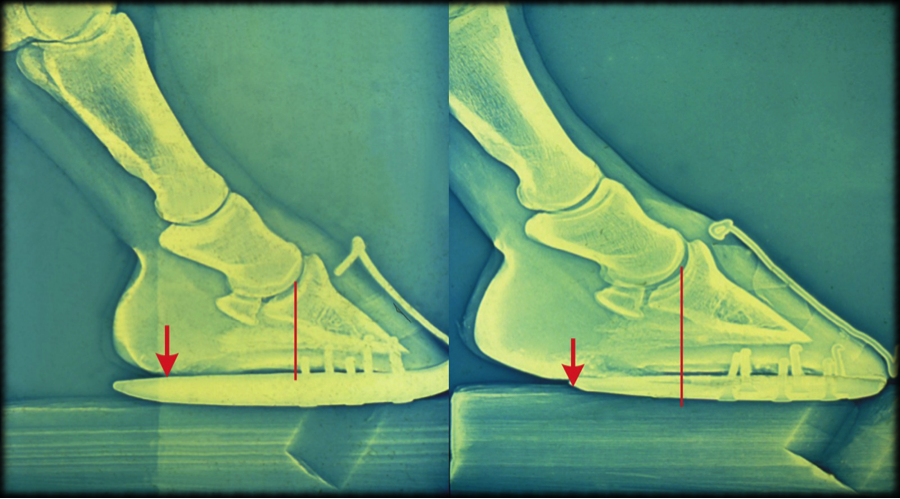

A horse with sore heels, right, has more than 50% of its foot behind the center of articulation. The last point of weight bearing is right over the wing of the coffin bone, which means that concussion is entering there and over the navicular area. The pastern joints also are experiencing pinching. One hour after a new trim and shoeing, left, the foot demonstrates improvement. The center is closer to 50/50, the joints are improved, and the last point of weight bearing is well behind the wing of the coffin bone. Photo courtesy of Grant Moon

An hour later, a second X-ray is taken, which reveals that the 50/50 split at the center of articulation is improved, as are the joints at the pasterns.

“I stuck a bit of shoe on the end to give it a bit of posterior support,” Moon explains. “If you draw a line at the last point of weight bearing, it’s way behind the wing of the coffin bone and way behind the navicular bone. So concussion is going to function much better. This horse didn’t leave sound, but it went out 75% better, just through shoeing.”